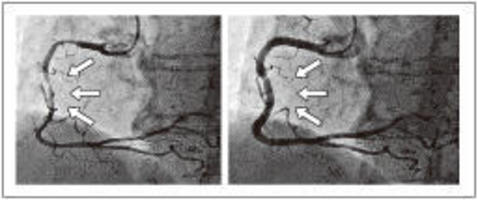

この時期に起きやすい心臓病の一つに冠攣縮(かんれんしゅく)性狭心症があります。動脈硬化による目詰まりの無い冠動脈が、急に異常収縮(冠攣縮)を起こして詰まってしまうのです。

冠動脈の血流量は自律神経によってコントロールされていますが、自律神経の嵐ではこの調節がうまくいかなくなり、冠動脈が過収縮を起こして閉塞(へいそく)してしまうのです。この病気は年齢に関係なく起こり、私の経験した最も若い患者は21歳の大学生でした。この方の冠攣縮は強烈で、左主幹部という最も太い部分が99%閉塞を起こすほどでした。